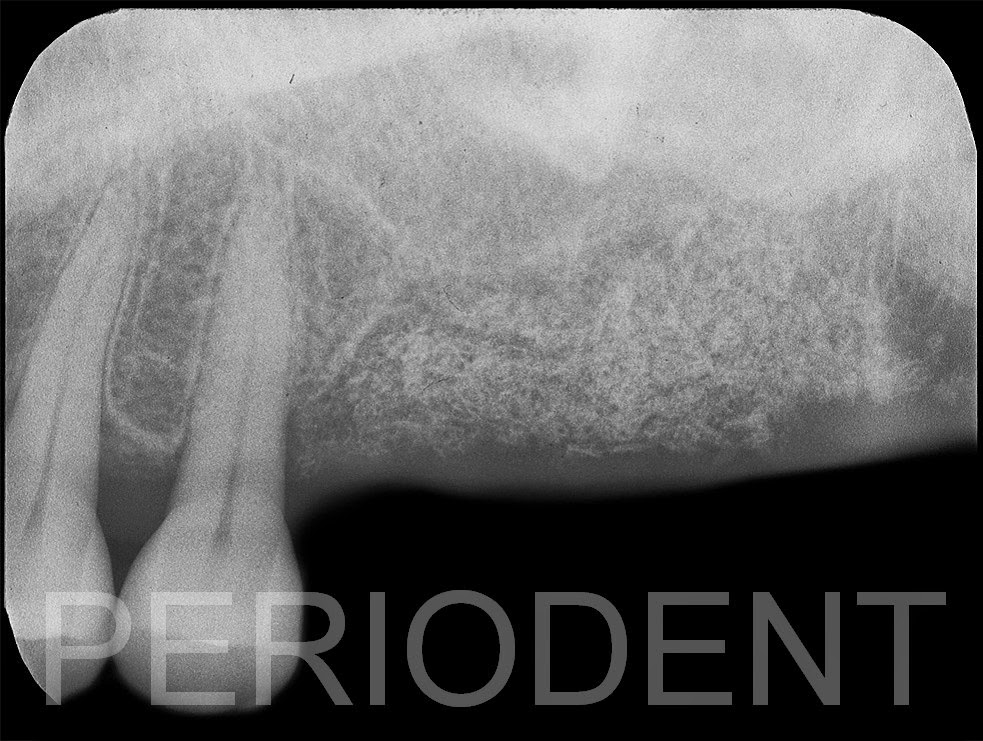

患者初診左上大臼齒有牙根分叉牙周病變,曾經牙周手術降低囊袋深度。

經過

15

年的觀察,左上大臼齒牙周破壞更加嚴重,且有嚴重動搖,決定拔除以植牙重建。